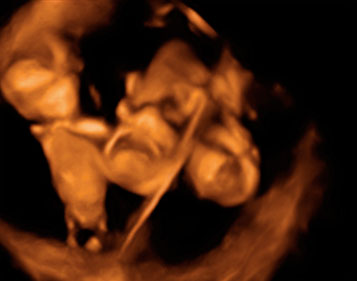

Ecografía 4D de la semana 15: Feto en rotación

El vídeo tomado por un ecógrafo en 4D muestra un feto de 15 semanas perfectamente conformado (cabeza, tronco, extremidades...) en una rotación.

Vídeo en rotación de un feto de 15 semanas

Así, en esta especie de "bloque", los especialistas pueden explorar otros planos del bebé o confirmar alguna patología. Llama la atención el grado de desarrollo físico que presentan los bebés con tan pocas semanas de gestación.